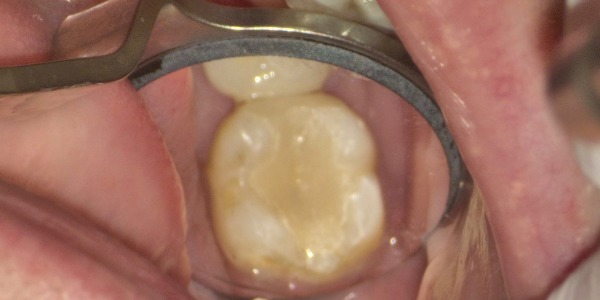

5日目 左下の1番奥の虫歯を取り除き、2本同時に型取りをしました。

6日目 セラミックの被せ物と詰め物を装着しました。